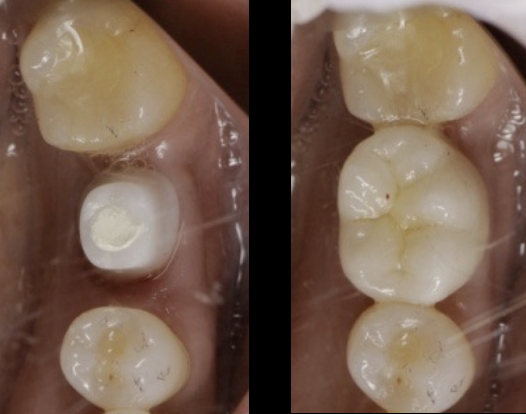

- 治療名

- インプラント

- 費用

- 1,262,100円(税込み)

内:オールセラミック1本/120,000円、インプラント1本/350,000円、 - 治療期間

- 2年

- 通院頻度

- 1ヵ月 2~3回

- そのほか患者様情報

- 56歳・女性

初診日 2008. 11. 8( 15年経過症例 )

治療内容

患者様の症状

- 8〜10年前から他の歯科医院にて治療を受けたが、見た目が良くない・噛めないとのことで再治療を希望された。アングルクラスⅠであった。右上前歯は小学生ののろ打撲。左下奥歯は歯根破折。

治療法

- 上顎右側前歯にインプラントを1本抜歯即時に埋入し、

- オールセラミックにて被せ物を行なった。

- 下顎左側臼歯に1本のインプラントを待時に埋入し、オールセラミッククランにて被せ物を行なった。

治療結果

- 審美的な仕上がりで、患者自身も満足した。15年経過し良好である。

現在は2〜3ヶ月おきのメインテナンス中である。